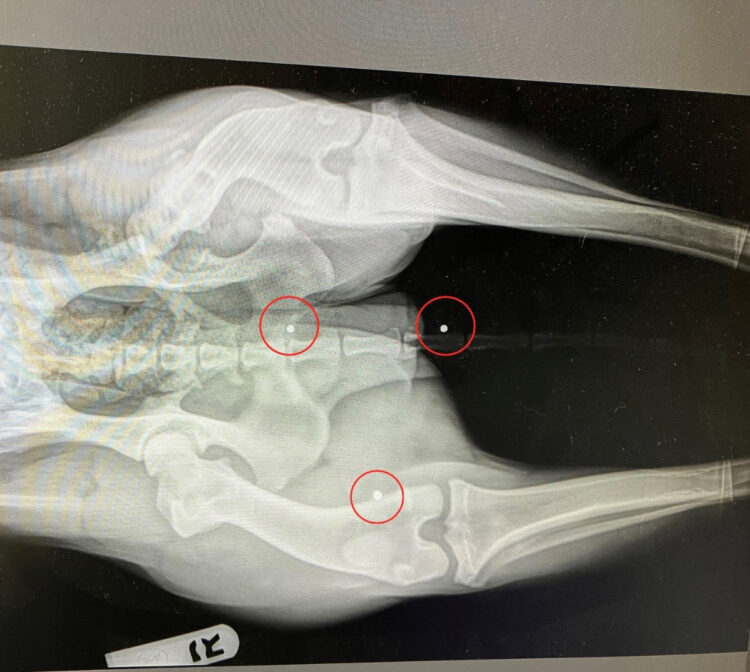

An X-ray found an old hip injury and also three BB pellets embedded into her tail, leg and spine.

Nutmeg will need an FHO, or femoral head ostectomy, surgery to help restore pain-free mobility. The BB pellets may be removed as well.

An X-ray showed three BB pellets in Nutmeg. Photo | Lake Norman Humane